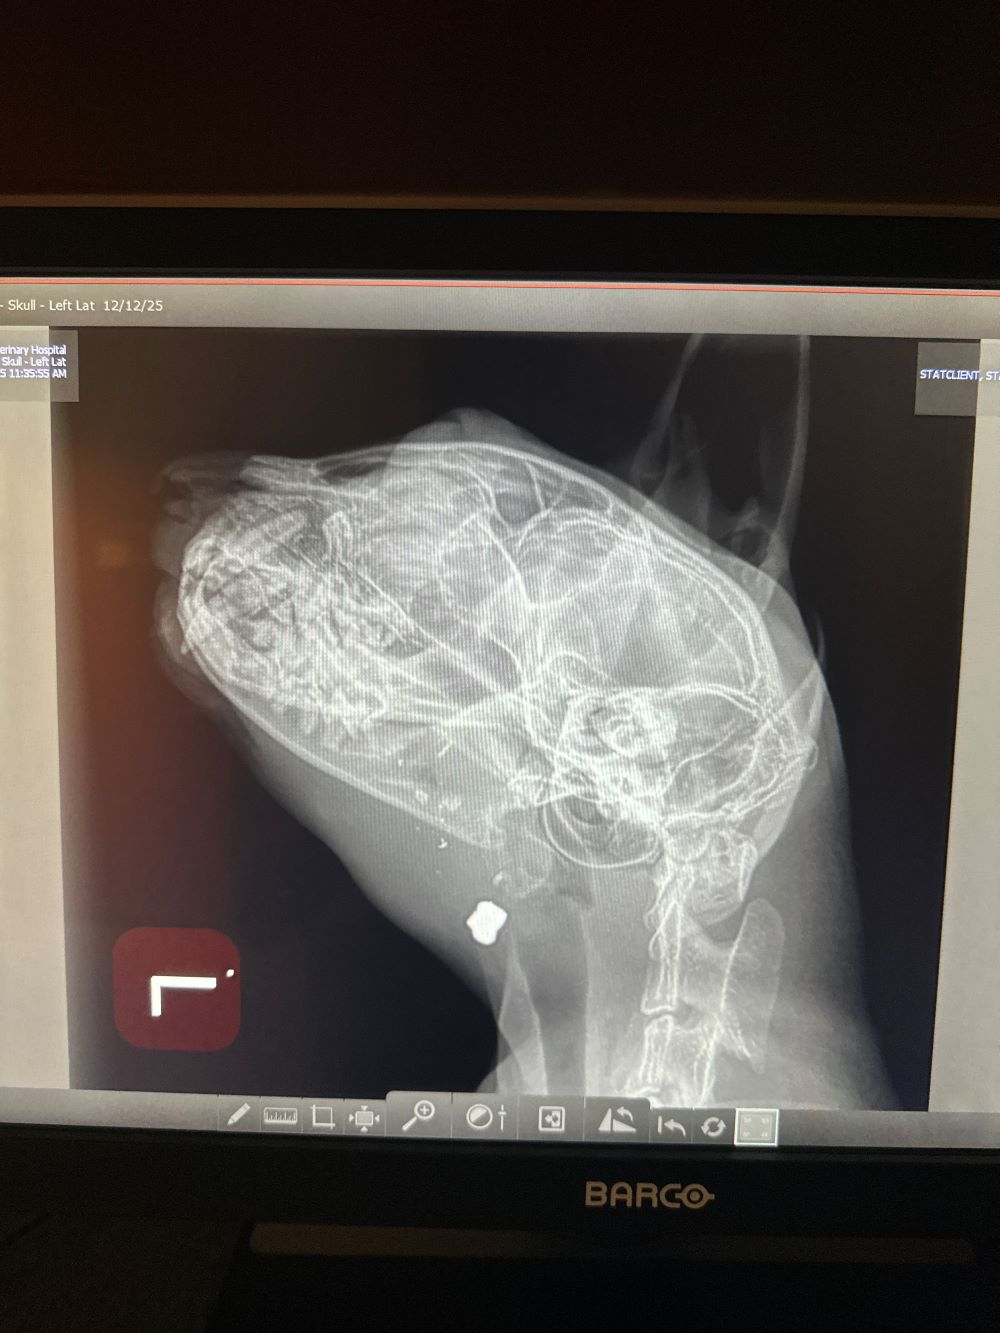

Right when we thought we were starting to get a breather, one of our longest residents surprised us with another emergency. Annie has struggled with seizures most of her life, but had gone almost 2 full years being seizure free. Between seizure episodes, she is a happy, affectionate, normal kitty who deserves life. She had a severe seizure episode back in February and again this week that landed her in the emergency vet, so after extensive consultations with her neurologist we have increased her phenobarbital dosage and are hoping this solves the problem, but it was an expensive trip to get the immediate seizure episode stabilized that we could use some help covering (and this is on top of her February bill for about the same amount that we still haven’t fully recouped).